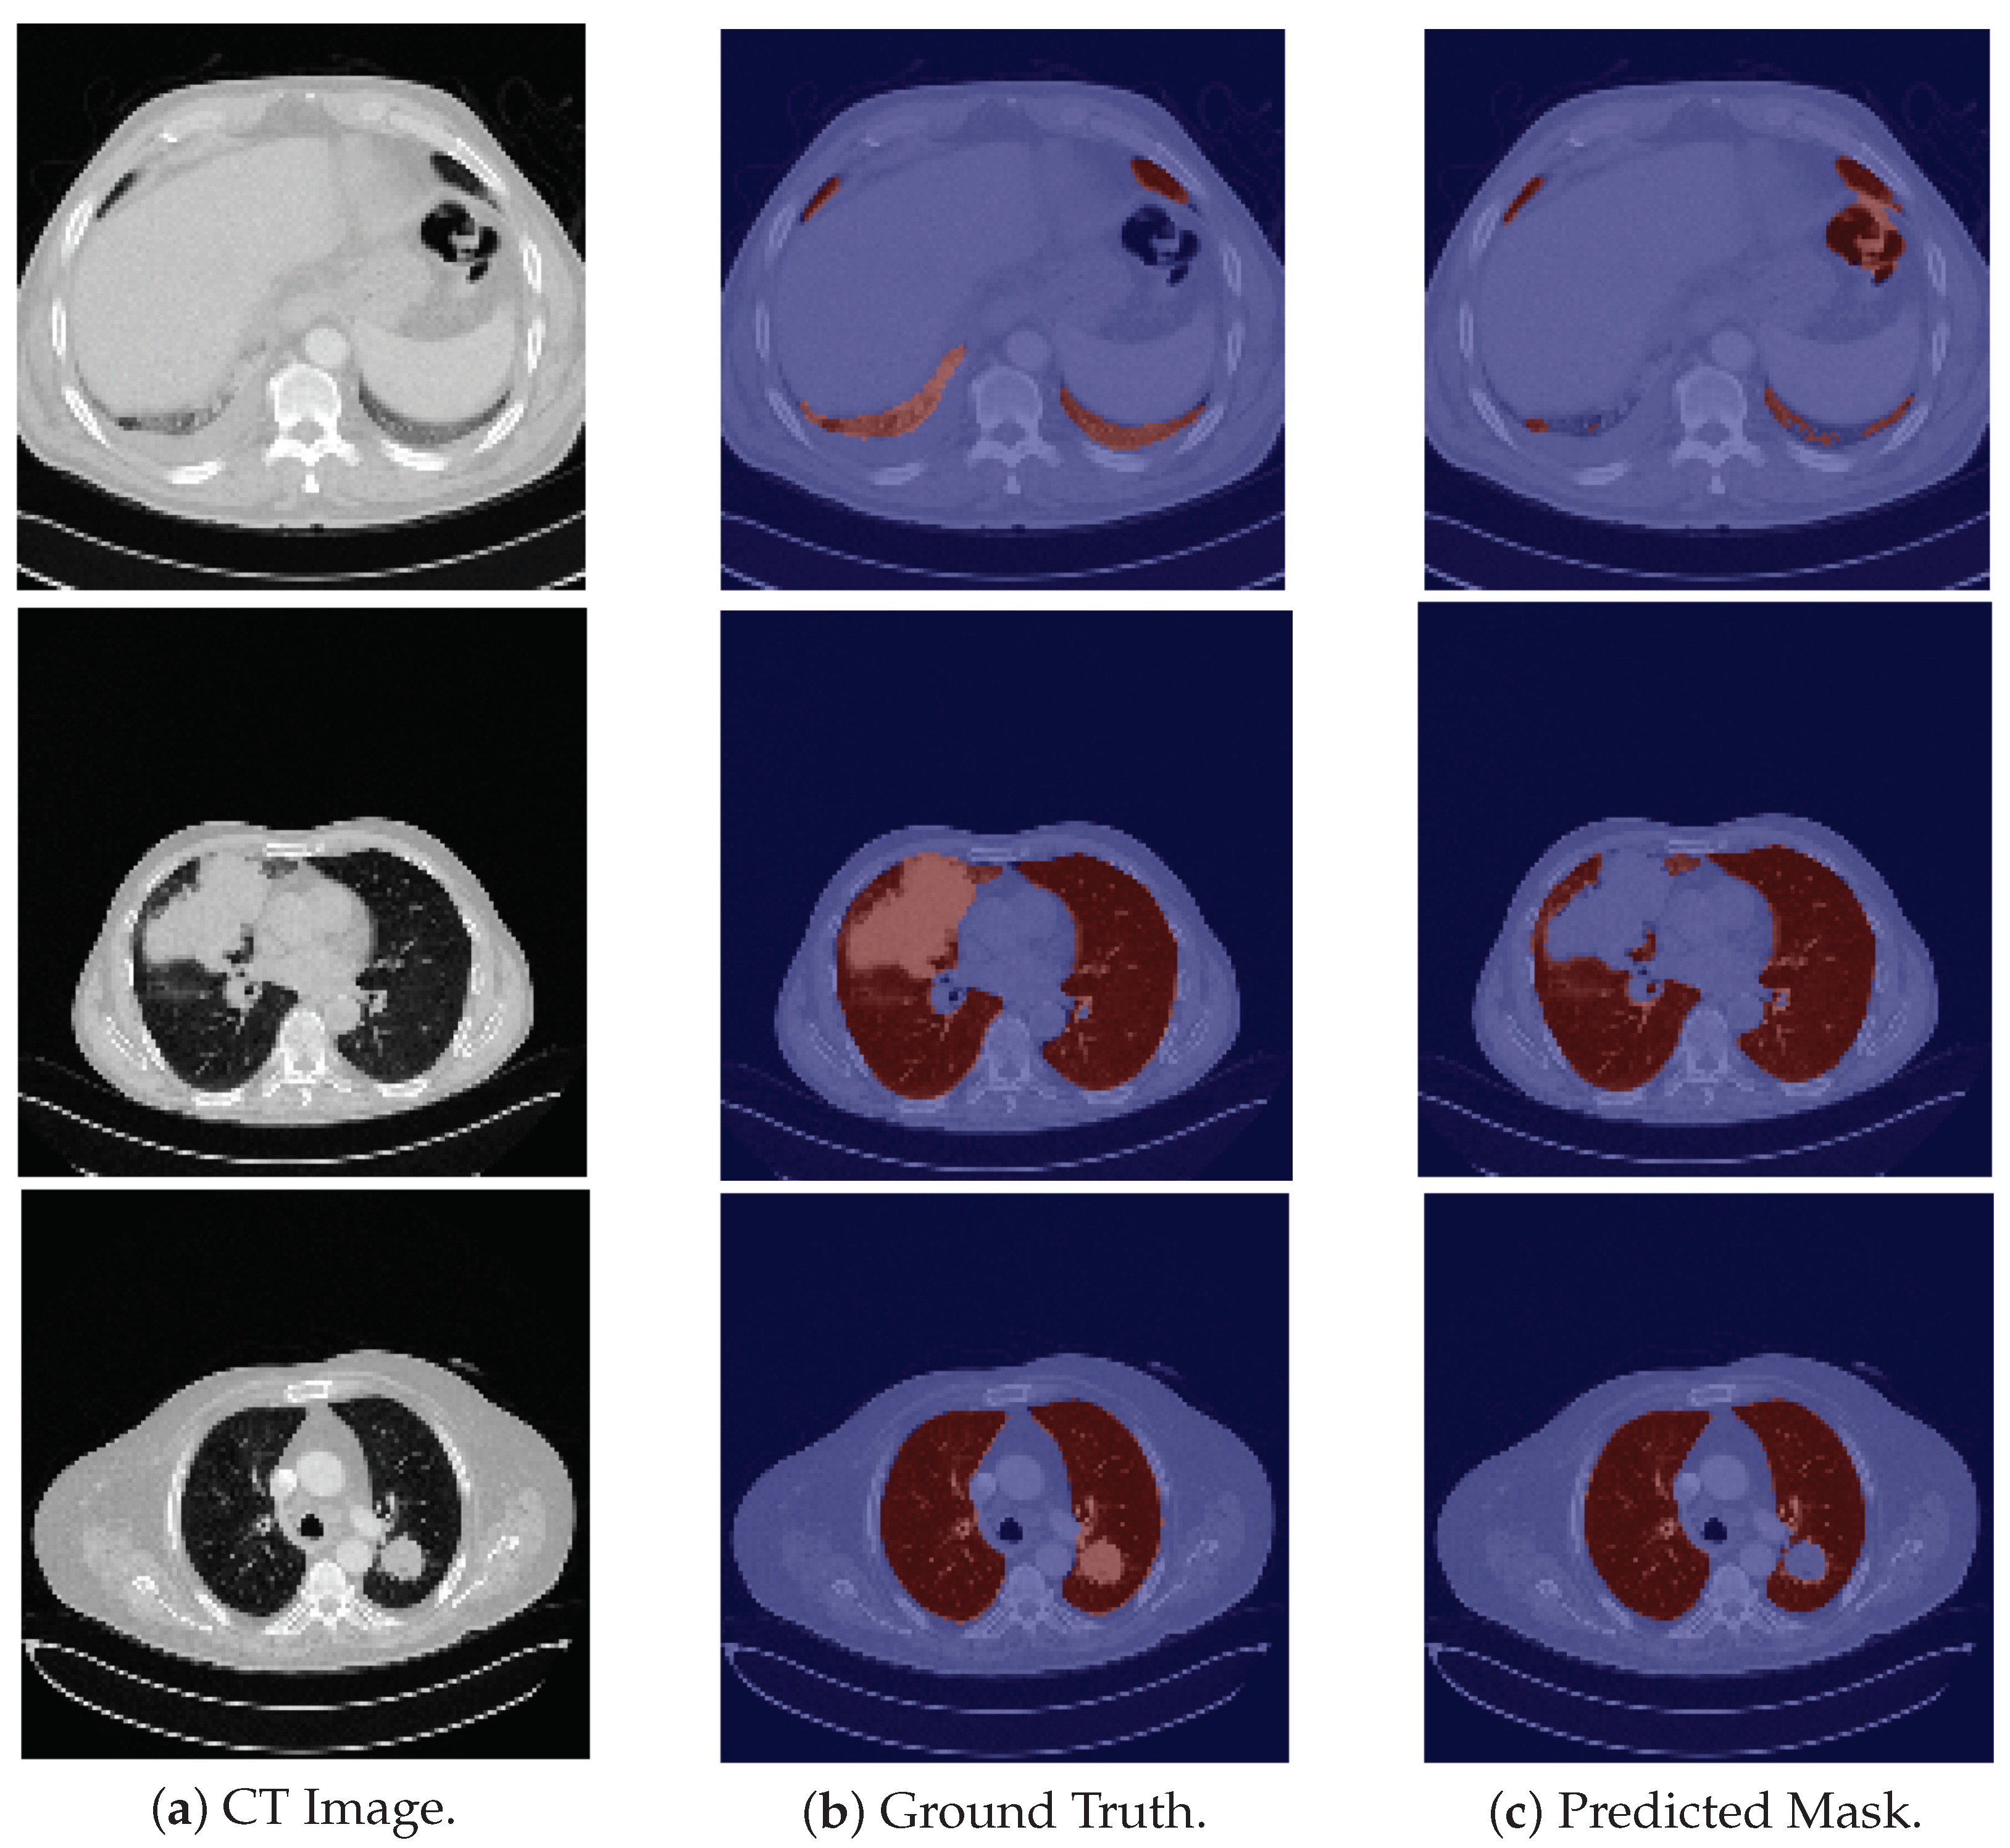

Regarding the HUG-ILD dataset, the model successfully segments the majority of scans and in some cases, it does not exclude pulmonary regions presenting a higher density. The model was also assessed on this dataset on a pattern level, i.e., each pattern was evaluated individually, to gain a better understanding of its behavior, and the results are presented in Table 5.

The results presented in Table 5 can be visually verified in Figure 3. For the specific cases of micronodules, bronchioectasis, emphysema, and some cases of fibrosis, the model is able to segment the entire lung area, as these are patterns which do not contain a higher contrast in tissues density (see respective examples on the first four rows of Figure 3). In general, those pathological cases showed a slightly better performance (Table 5).

In contrast, for cases of macronodules, reticulation, consolidation, ground-glass, and pneumocystis carinii pneumonia, the model presents a difficulty in performing such tasks in the regions of higher density (see last five examples (rows) of Figure 3). Besides that, the scans from this dataset include the trachea and other respiratory structures (apart from the lungs) in their ground truth, elements that are not identified by the model, and thus contributing to a lower metric (see rows two–five in Figure 3). Once again the model fails to identify the slices corresponding to the base of the lung (see the second row in Figure 6).

Another limitation comes from the annotations of the datasets. Those annotations come from different projects and followed different segmentation guidelines. There is no consensus on the inclusion/exclusion of some structures, such as airways or tumor masses. Examples of airways inclusion are shown in the second, third, fourth, and fifth rows in Figure 3 that belong to the HUG-ILD dataset, and examples of airways exclusion are shown in the last row in Figure 2, the first row in Figure 4, and the last row in Figure 5, that belong to the LCTSC, VESSEL12, and CHUSJ datasets, respectively. Examples of tumor masses inclusion are shown in last two rows in Figure 5 that belong to the CHUSJ dataset, and examples of exclusion are shown in the last row in Figure 2 that belong to the LCSTC dataset. Ideal, a very objective protocol of segmentation should be followed for the entire dataset annotation (training and test set) in order to not create label noise, which is responsible for overall quantitative performance degradation.

Figure 3. Examples of HUG-ILD images for pathological cases. The patterns of these images from top to bottom are, respectively, micronodules, bronchioectasis, emphysema, fibrosis, macronodules, reticulation with ground-glass, consolidation, ground-glass, and pneumocystis carinii pneumonia. For the last five examples, the model failed to segment part of the lung due to the pathological changes present in the image.